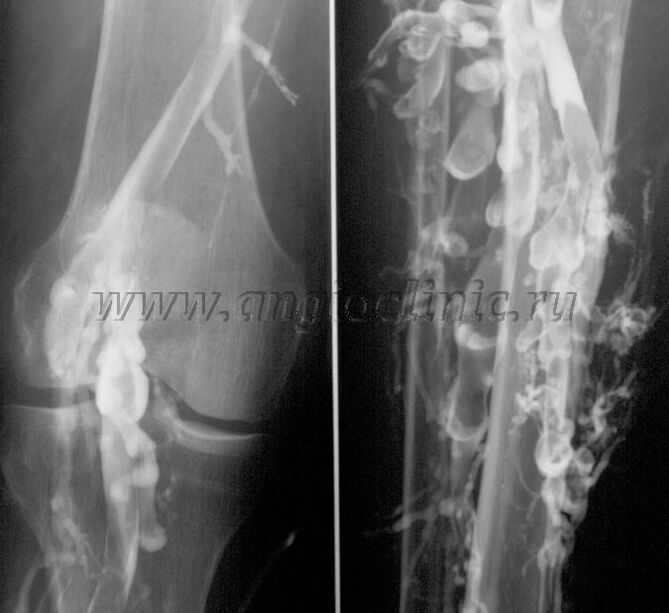

Flebografia kontrastowa

Zwykle do pełnego rozpoznania patologii żylnej wystarcza badanie ultrasonograficzne, jednak w niektórych przypadkach konieczne jest zbadanie zależności pomiędzy stanem układu żył głębokich i powierzchownych, szczególnie w przypadku nawrotów żylaków i żylaków wtórnych.

Aby rozwiązać te problemy, stosuje się kontrastowe badanie rentgenowskie. Nakłuwa się żyły odpiszczelowe i podaje kontrast. Ruch kontrastu obserwuje się na monitorze aparatu rentgenowskiego, przeprowadza się wszelkie niezbędne badania i projekcje. Obecnie flebografię w leczeniu żylaków stosuje się bardzo rzadko.